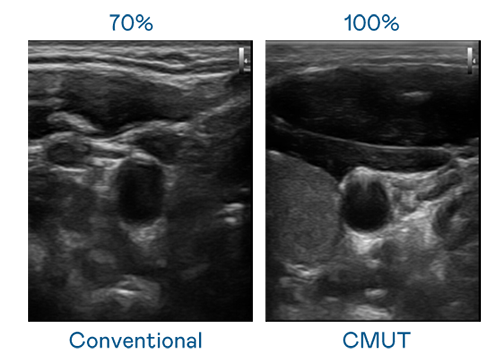

CMUT 技术是一种用电容式微机电元件来产生超音波讯号的技术。与传统 PZT 压电式技术相比,CMUT 频宽增加 30%,更宽频的超音波讯号让影像解析度大幅提升,是实现高影像品质医疗超音波扫描、促进精准医疗发展的关键技术。

大频宽带来超清晰影像

超音波影像的解析度高低,首先取决于探头能发出的讯号频宽。VR彩票 CMUT 可提供高清晰的超音波讯号,提供高频宽、高灵敏度、影像纹理细节更高的超音波影像,协助医护人员缩短影像判读时间及利用精准的医疗影像进行诊断。